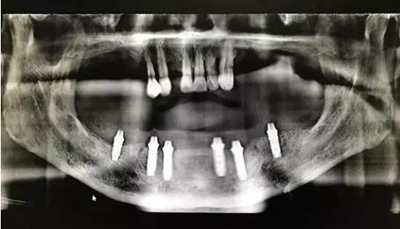

患者男,喜歡抽煙喝茶,有重度牙周病,下頜的牙齒已經(jīng)完全拔除,上頜牙齒在CT中可見,牙槽骨吸收很嚴(yán)重,牙根部分暴露,粘膜萎縮。要求:進(jìn)行下半口固定義齒即刻修復(fù)。

從CT可以看出患者前牙區(qū)牙槽骨非常薄,有的地方3.5mm不到,左側(cè)4號(hào)牙位有嚴(yán)重的骨吸收,需要進(jìn)行植骨,后牙區(qū)離神經(jīng)管較近,設(shè)計(jì)種植短粗型種植體。

通過術(shù)前精確的設(shè)計(jì),避開了患者骨壁較薄需要做骨劈開的區(qū)域,避免了大翻瓣造成較大創(chuàng)傷,大大提高了患者的舒適度。

全程手術(shù)采用小翻瓣微創(chuàng)種植,選擇初期穩(wěn)定性較好的植體進(jìn)行即刻負(fù)重。整個(gè)手術(shù)從開始到最終戴上臨時(shí)牙,只花費(fèi)2個(gè)小時(shí)的時(shí)間,就讓患者恢復(fù)了完美笑容。數(shù)字化種植為醫(yī)生和患者帶來不一樣的感受!